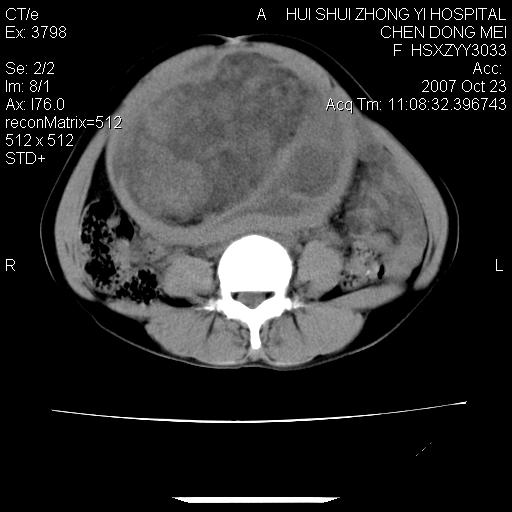

标题: CT10156:女.43岁,发现中下腹部包都块2年 [打印本页]

标题: CT10156:女.43岁,发现中下腹部包都块2年

发现中下腹部包都块2年。2年来月经不规律。

腹腔巨大软组织密度影,边缘光滑,包膜完整,内囊变坏死。腹膜后及盆腔内淋巴结肿大。结合病史考虑卵巢癌可能性大。

病变巨大,呈囊实性改变,包膜较厚且完整,内见分膈,周围脏器明显受压移位,病变与左侧附件关系密切,考虑来源左侧附件的囊腺瘤,不除外癌变可能;畸胎瘤可能性较小。

病变巨大,呈囊实性改变,包膜较厚且完整,内见分膈,周围脏器明显受压移位,病变与左侧附件关系密切,考虑来源左侧附件的囊腺瘤,盆腔内见肿大淋巴结,不除外癌变可能。

病变巨大,呈囊实性改变,包膜较厚且完整,内见分膈,周围脏器明显受压移位,病变与左侧附件关系密切,考虑来源左侧附件的囊腺瘤,不除外癌变可能